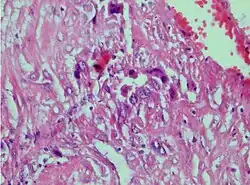

| Photomicrograph showing proliferating intermediate trophoblast with scarce cytotophoblastic and syncytiotrophoblastic elements | |

A placental site trophoblastic tumor is a monophasic neoplasm of the implantation site intermediate trophoblast, and usually a benign lesion, which comprises less than 2% of all gestational trophoblastic proliferations. Preceding conditions include molar pregnancy (5%). Compared to choriocarcinoma or invasive mole, hemorrhage is less conspicuous and serum β-HCG level is low, making early diagnosis difficult.

Immunohistochemistry often shows positive staining for hPL,[4][5] keratin,[5] Mel-CAM,[5] and EGFR.,[4] This immunohistochemical profile, particularly the strong positivity for hPL and Mel-CAM, along with the negative or focal staining for β-hCG and p63, helps distinguish PSTT from other types of gestational trophoblastic neoplasia such as choriocarcinoma and epithelioid trophoblastic tumour.[5]